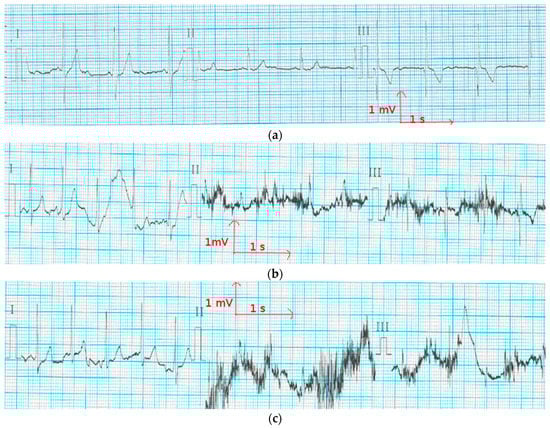

3.3. Evaluation of Textile Electrodes in ECG Monitoring